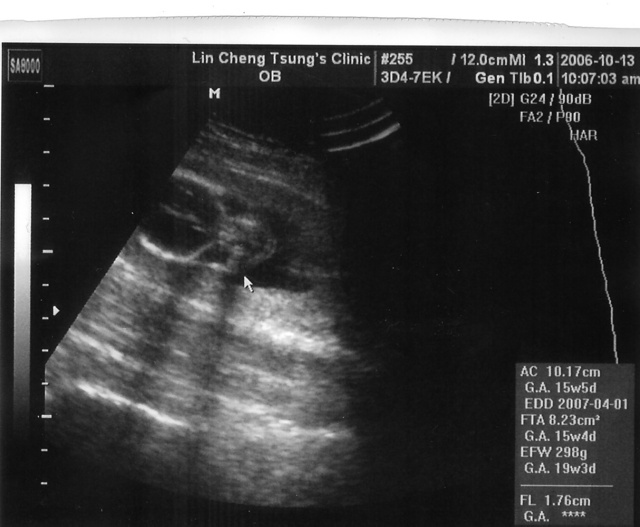

2006.10.13

可以看到小朋友的輪廓了

,那張臉看起來有些奇妙,另外沒有列印出來的照片裡(感覺起來一次產檢只能照一張照片似的)可以看出脊椎骨已經長出來了,除了手腳骨都正常,雙手雙腳的五個指頭都看得很清楚,現在頭寬3.4cm,胸圍10.1cm,大腿骨長1.8cm,據醫生說比例正常沒有異狀,不過也許小朋友看起來小了點,所以預產期又向後延了幾天。

每次產檢結果都不會完全一樣哩,小朋友說是差兩天就滿十六週,這而預產期又變成四月二號了,給的解釋是老婆月經週期不一樣很準確所以時間判斷上會有所不同。然後醫生變得不確定小朋友是男生還是女生,說是看起來像是小鳥的地方有點小,怕說是胎盤臍帶的陰影造成的誤差。其實我一直覺得男生女生都好,但是麻煩醫生不要呼弄我就好,不然我每次跟小朋友說話說錯他聽了性別錯亂怎麼辦,再等一兩個月才會比較確定,屆時在跟各位報告!思考換一家醫院產檢中~~~